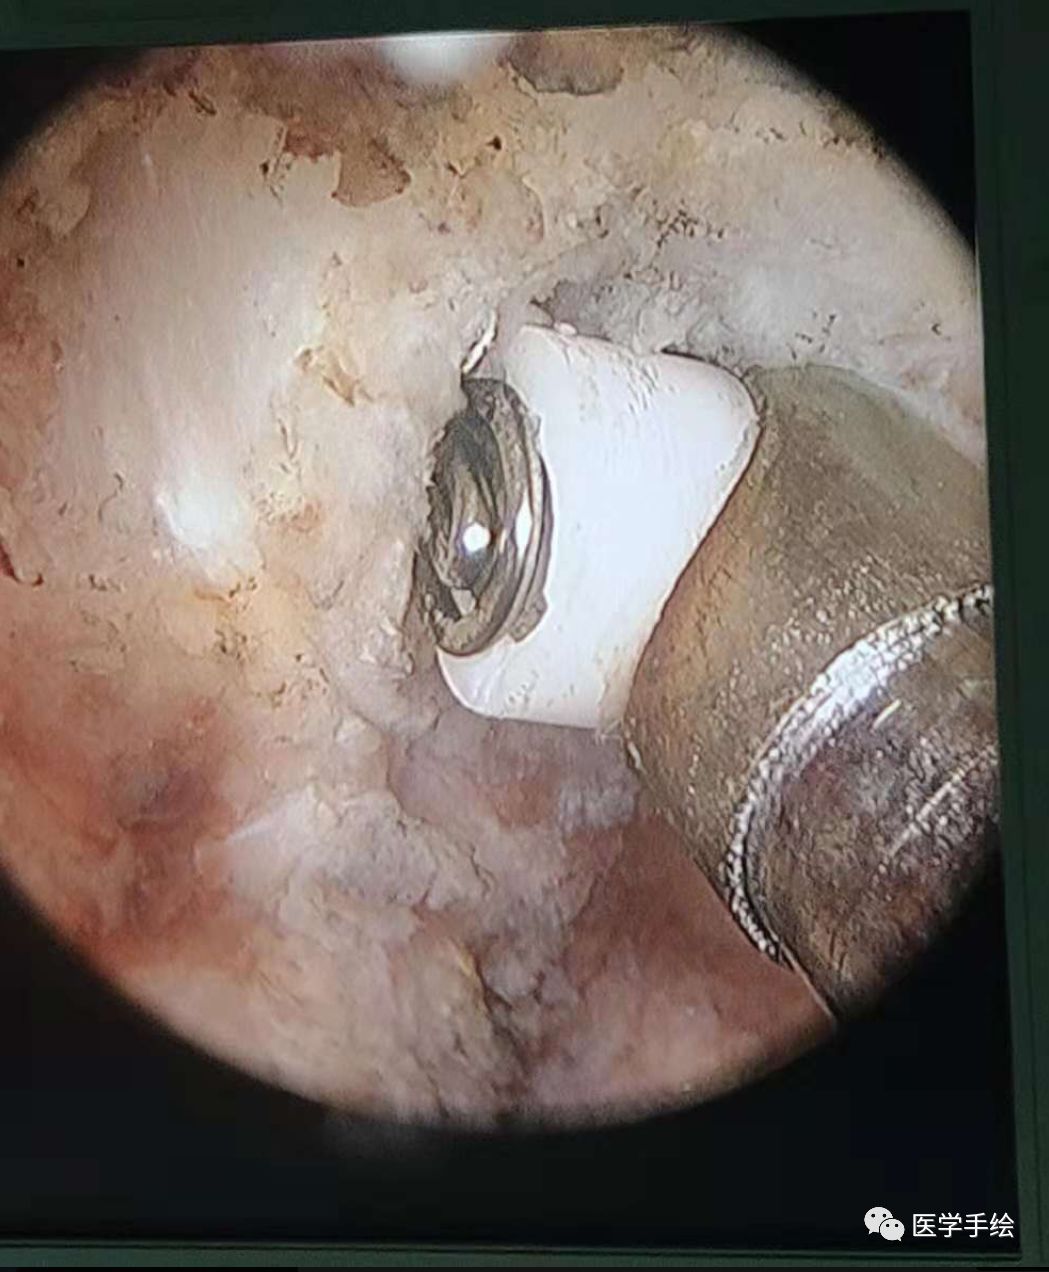

3、插入关节镜,用关节镜射频刀头清理椎板间隙表面的肌肉组织,显露上下椎板。

4、可以通过椎板咬骨钳及关节镜磨钻处理椎板下缘及关节突关节。

5、寻找黄韧带与椎板的破口位置,这时可以通过刮匙剥离。安全迅速地“破黄”是该技术的关键。

6、神经剥离子剥离神经显露突出的间盘,射频刀头止血,髓核钳摘除突出髓核组织。